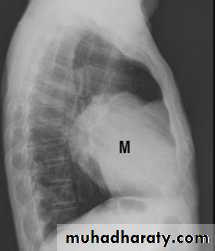

Can be useful in lung CA when questions can not be answered by CT and can show intraspinal Extensions of med. Neural tumorsHorizontal fissure

Intrathoracic mass

intrasp. portionSp. cord

Neurofibroma MRI with intrasp. Extension